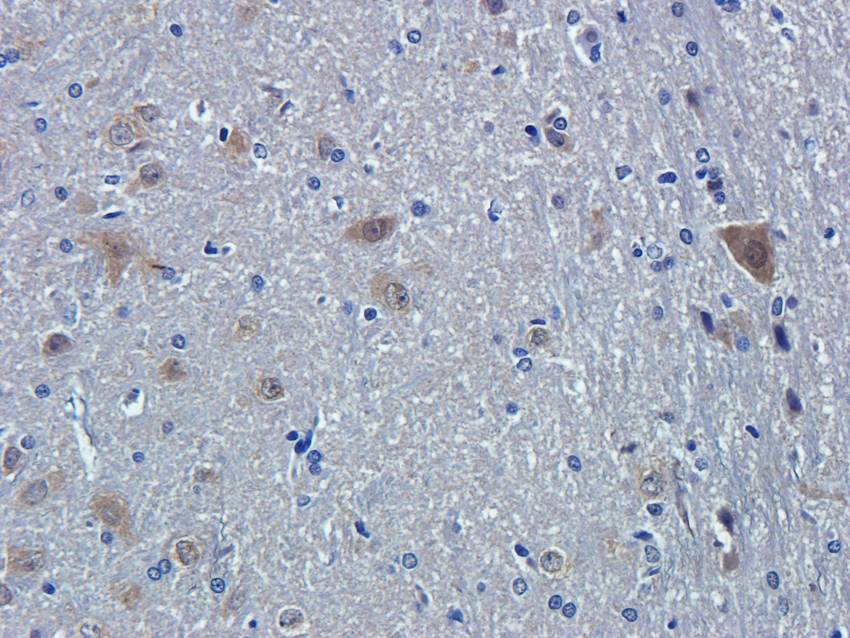

IHC staining of FFPE human brain with Ubiquitin antibody (clone PBQN-1). Required HIER: boil tissue sections in pH9 10mM Tris with 1mM EDTA for 10-20 min followed by cooling at RT for 20 min.